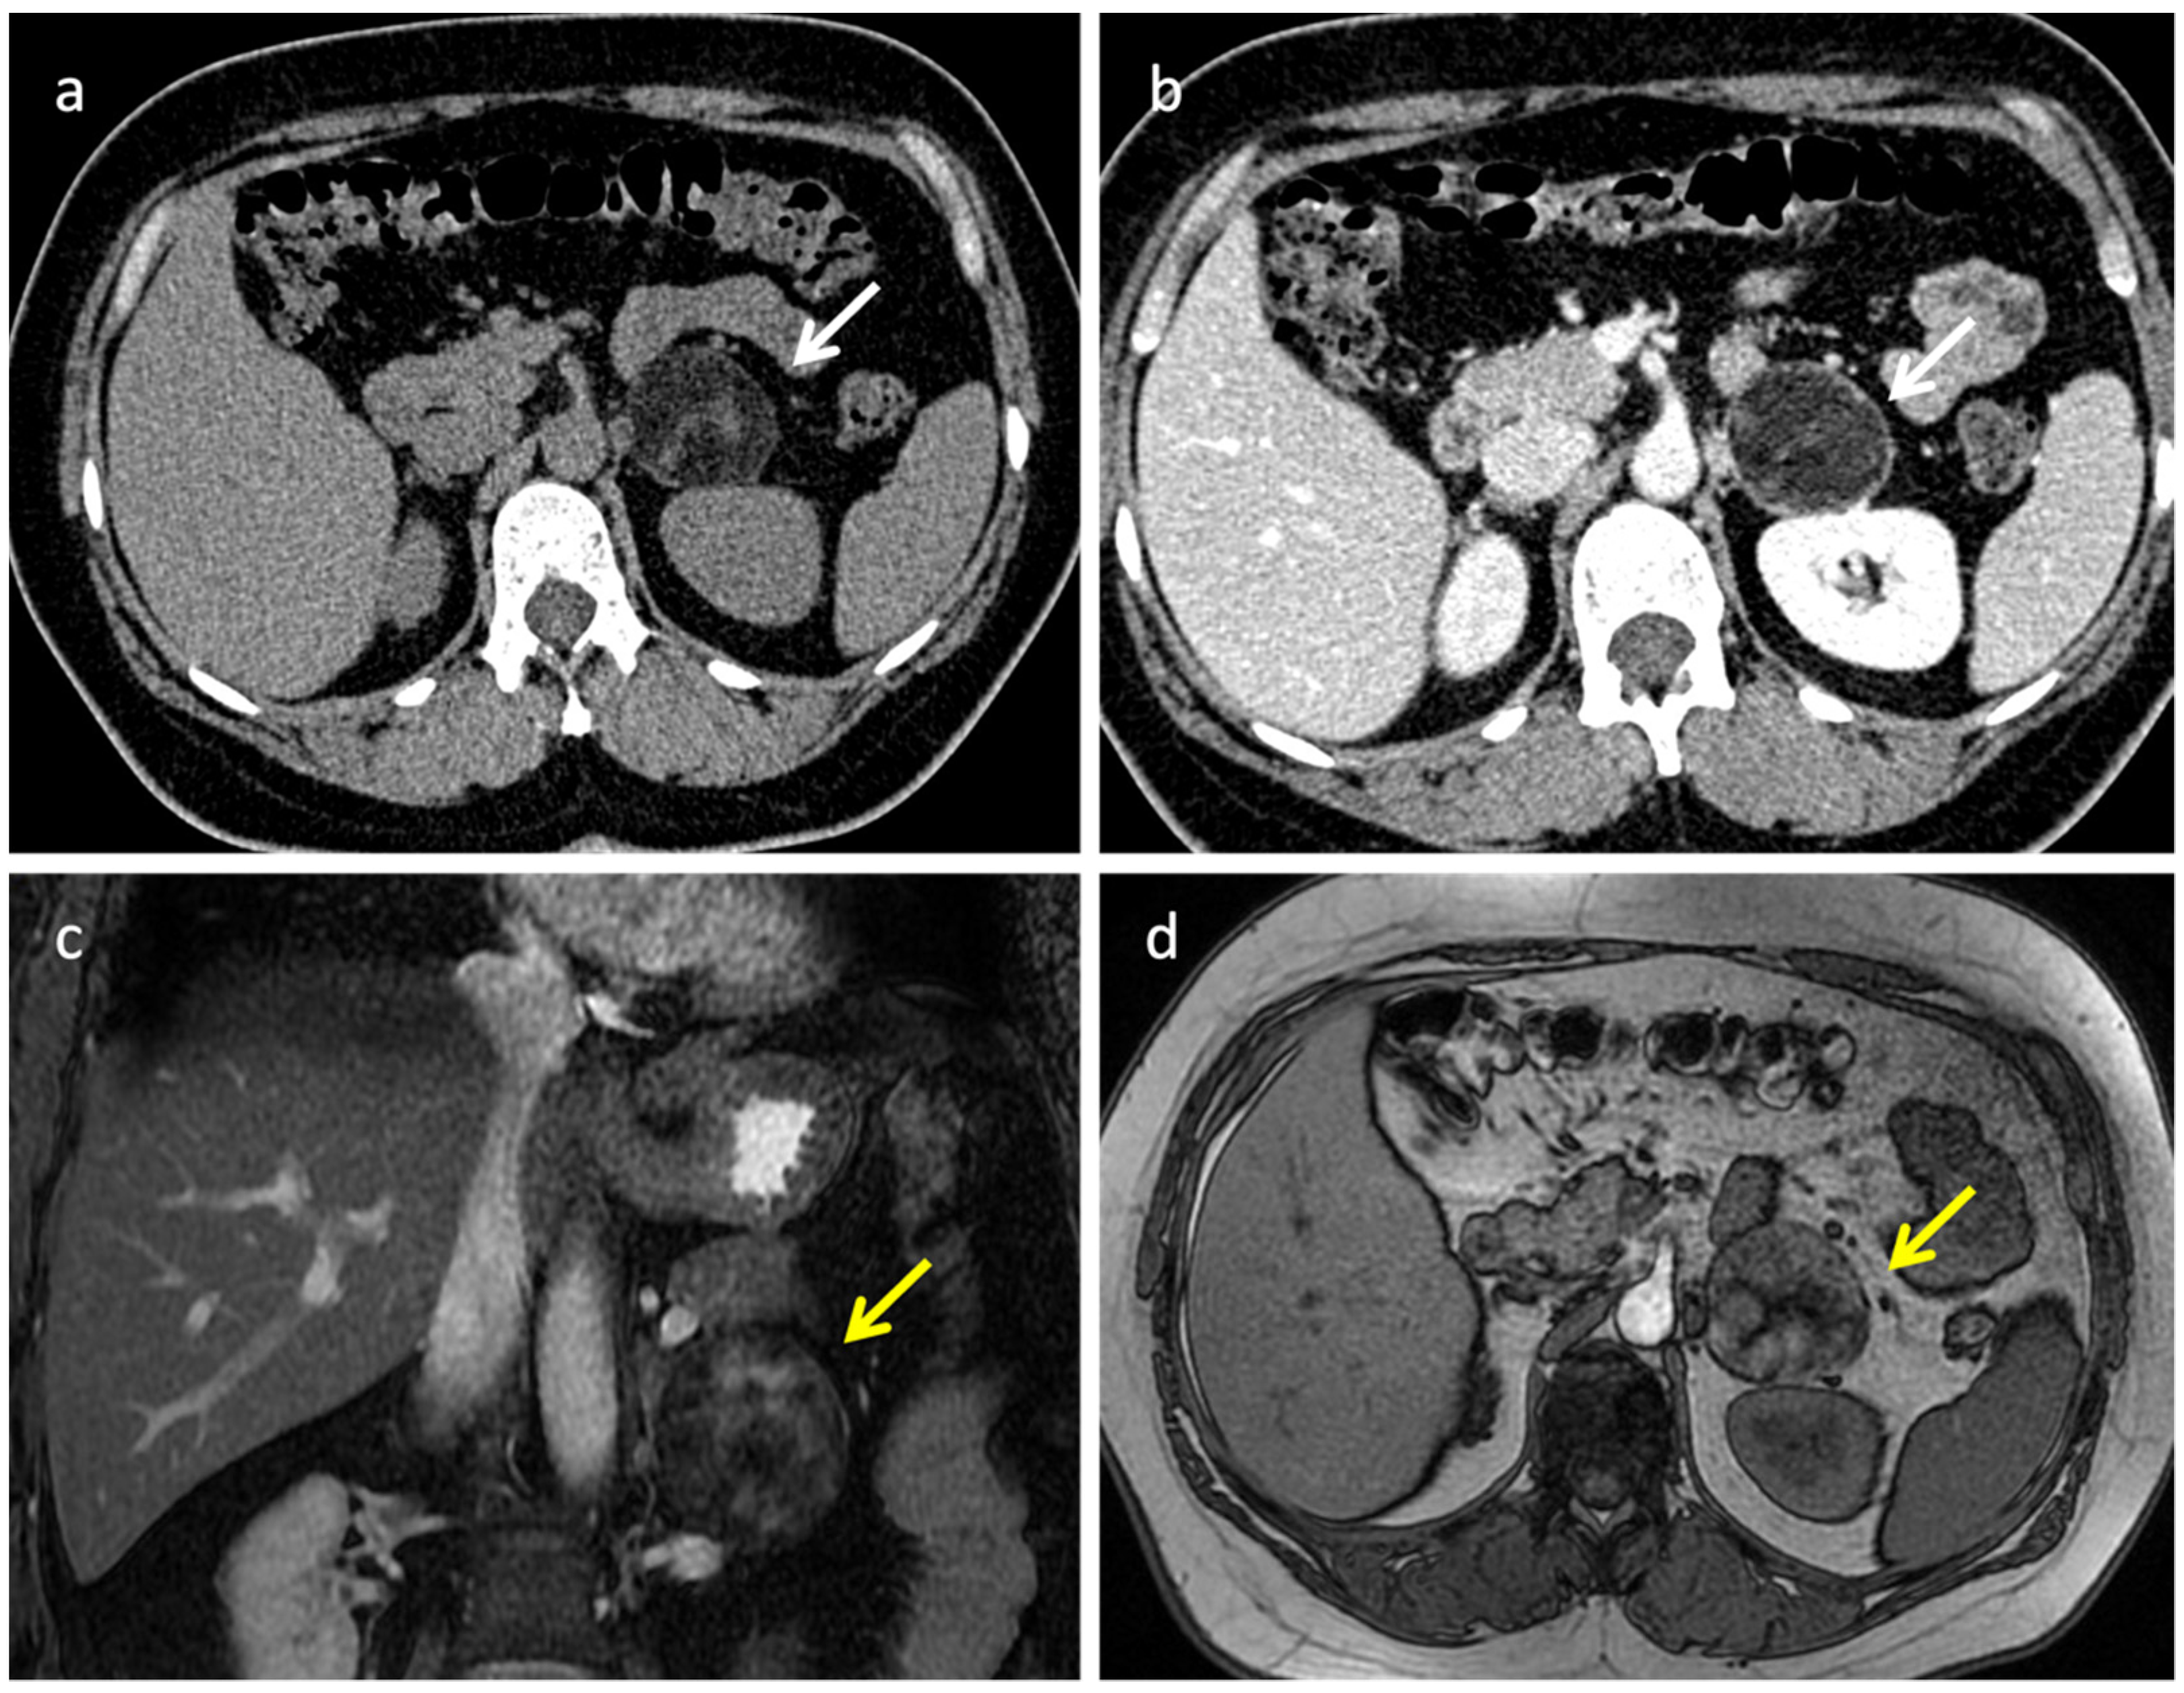

3.1. Pheochromocytoma